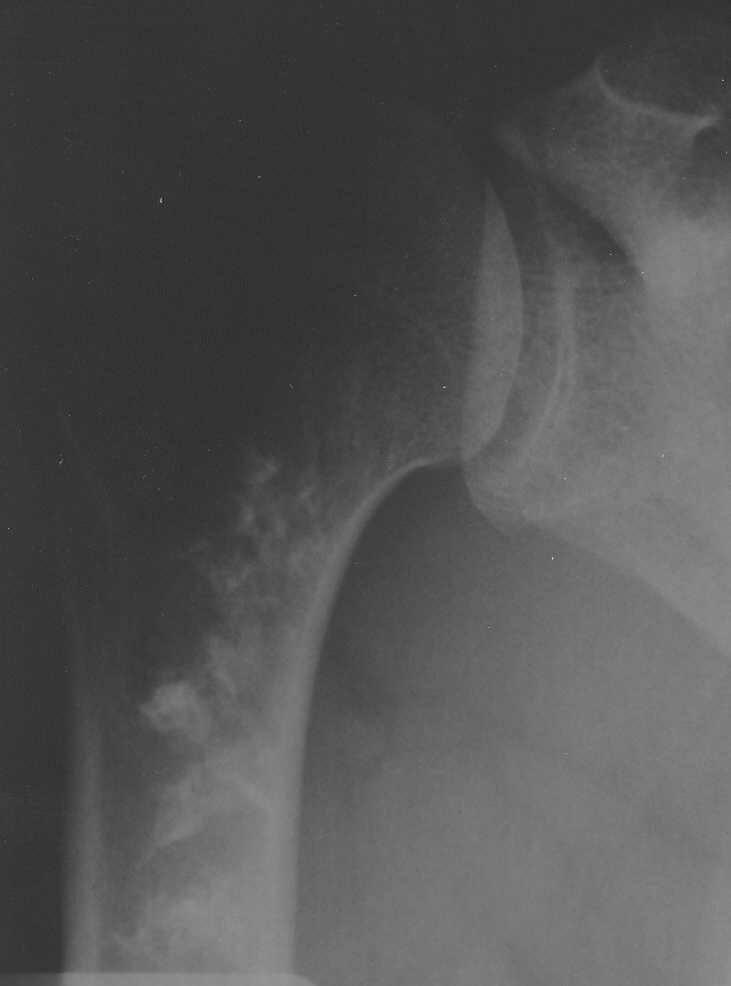

На снимках картина похожа на ENCHONDROMA

Если пациент бессимптомный - только наблюдение. Если пациент симптоматичный - стандртный протокол обследования - как при подозрении на chondrosarcoma.

Уважаемый Лев, изначально была мысль насчет опухоли хрящевого генеза, но смущает факт большой множественности очагов затемнения. К тому же, очень скудная клиническая симптоматика. Травм не было. Боли возникли внезапно несколько месяцев назад, только при движениях.

Мноэжественные очаги не исключают хрящевую опухоль.Ядумаю что надо сделать обследование - начать с BONE SCAN и анализов крови - cbc,esr,crp, alk.phosph

Недавно выполнял биопсию по поводу аналогичных очагов в бедренной кости, подозревали оссифицирующую энхондрому, оказалось - участки некроза с

оссификацией (у пациентки в анамнезе лимфогранулематоз и 18 курсов ПХТ).

Советую сделать биопсию, чтобу не гадать на кофейной гуще.